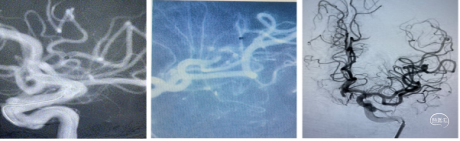

术前CTA

手术过程

1、行右侧股动脉穿刺并置入8F动脉鞘成功。造影发现左侧大脑中动脉M3段以

远显影欠佳。正位不清晰,斜位清晰可见M3闭塞。

2、5F 125cm 中间导管抽吸:

泥鳅导丝引导8F导引导管至左侧颈内动脉C1远端平直处建立通路,微导丝引导微导管及5F 125cm 中间导管到达左侧大脑中动脉M3闭塞段近端。

近端使用60mL注射器手动抽吸两次,未见血栓取出。可能为导管未能接触血栓。

注意: 6F 125cm 中间导管到达大脑中动脉M1段; 5F 125cm中间导管到达大脑中动脉M2分叉以远。

3、换用3MAX 抽吸导管通路组合:

8F MPA+3MAX抽吸导管+微导丝,抽吸两次后栓子逃逸至远端分叉部。

5、 再次跟进3MAX抽吸一次,完全再通。

术后即刻复查XperCT未见出血。